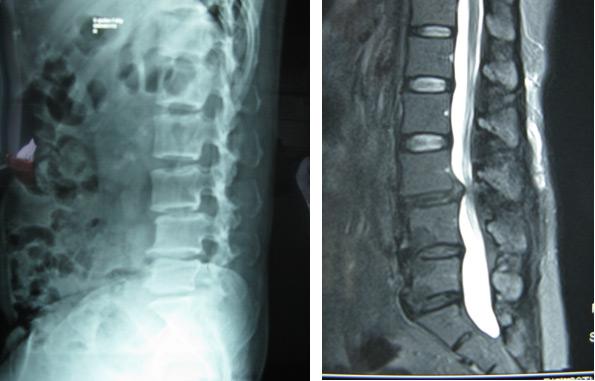

患者李某,男,38 岁,腰椎间盘突出症(L5/S1)如上图核磁共振检查所示:术中操作

术中染色的髓核组织   术后 MRI 像提示突出椎间盘切除彻底